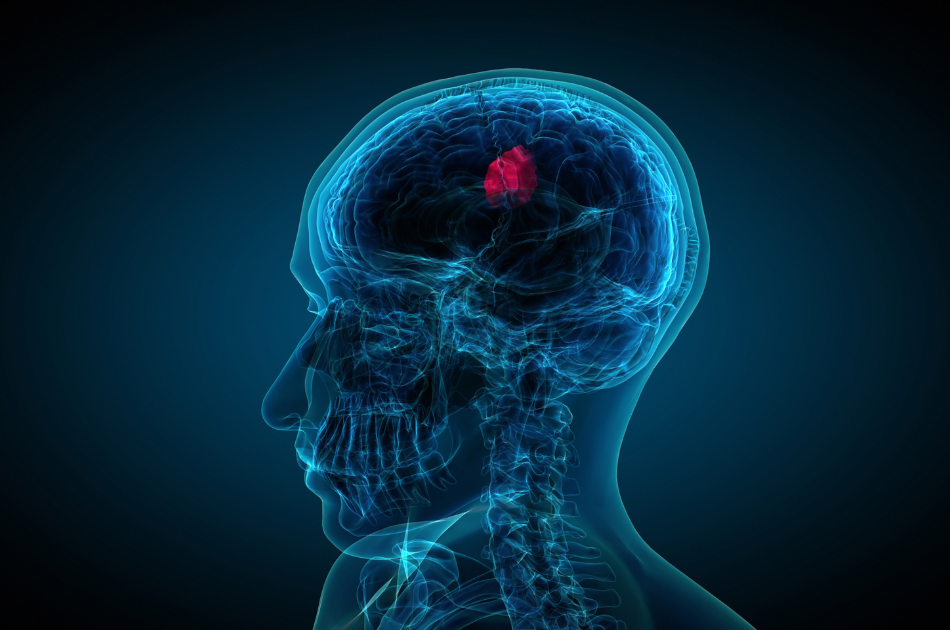

Cancer therapy breakthrough: X-rays expose and exterminate brain tumor cells with precision

A revolutionary study from Nanyang Technological University in Singapore (NTU Singapore) developed a novel way to selectively target and destroy brain tumor cells using extremely low-dose X-rays. Radiodynamic therapy, a novel treatment, stopped tumor development and doubled survival time in animal Read More...